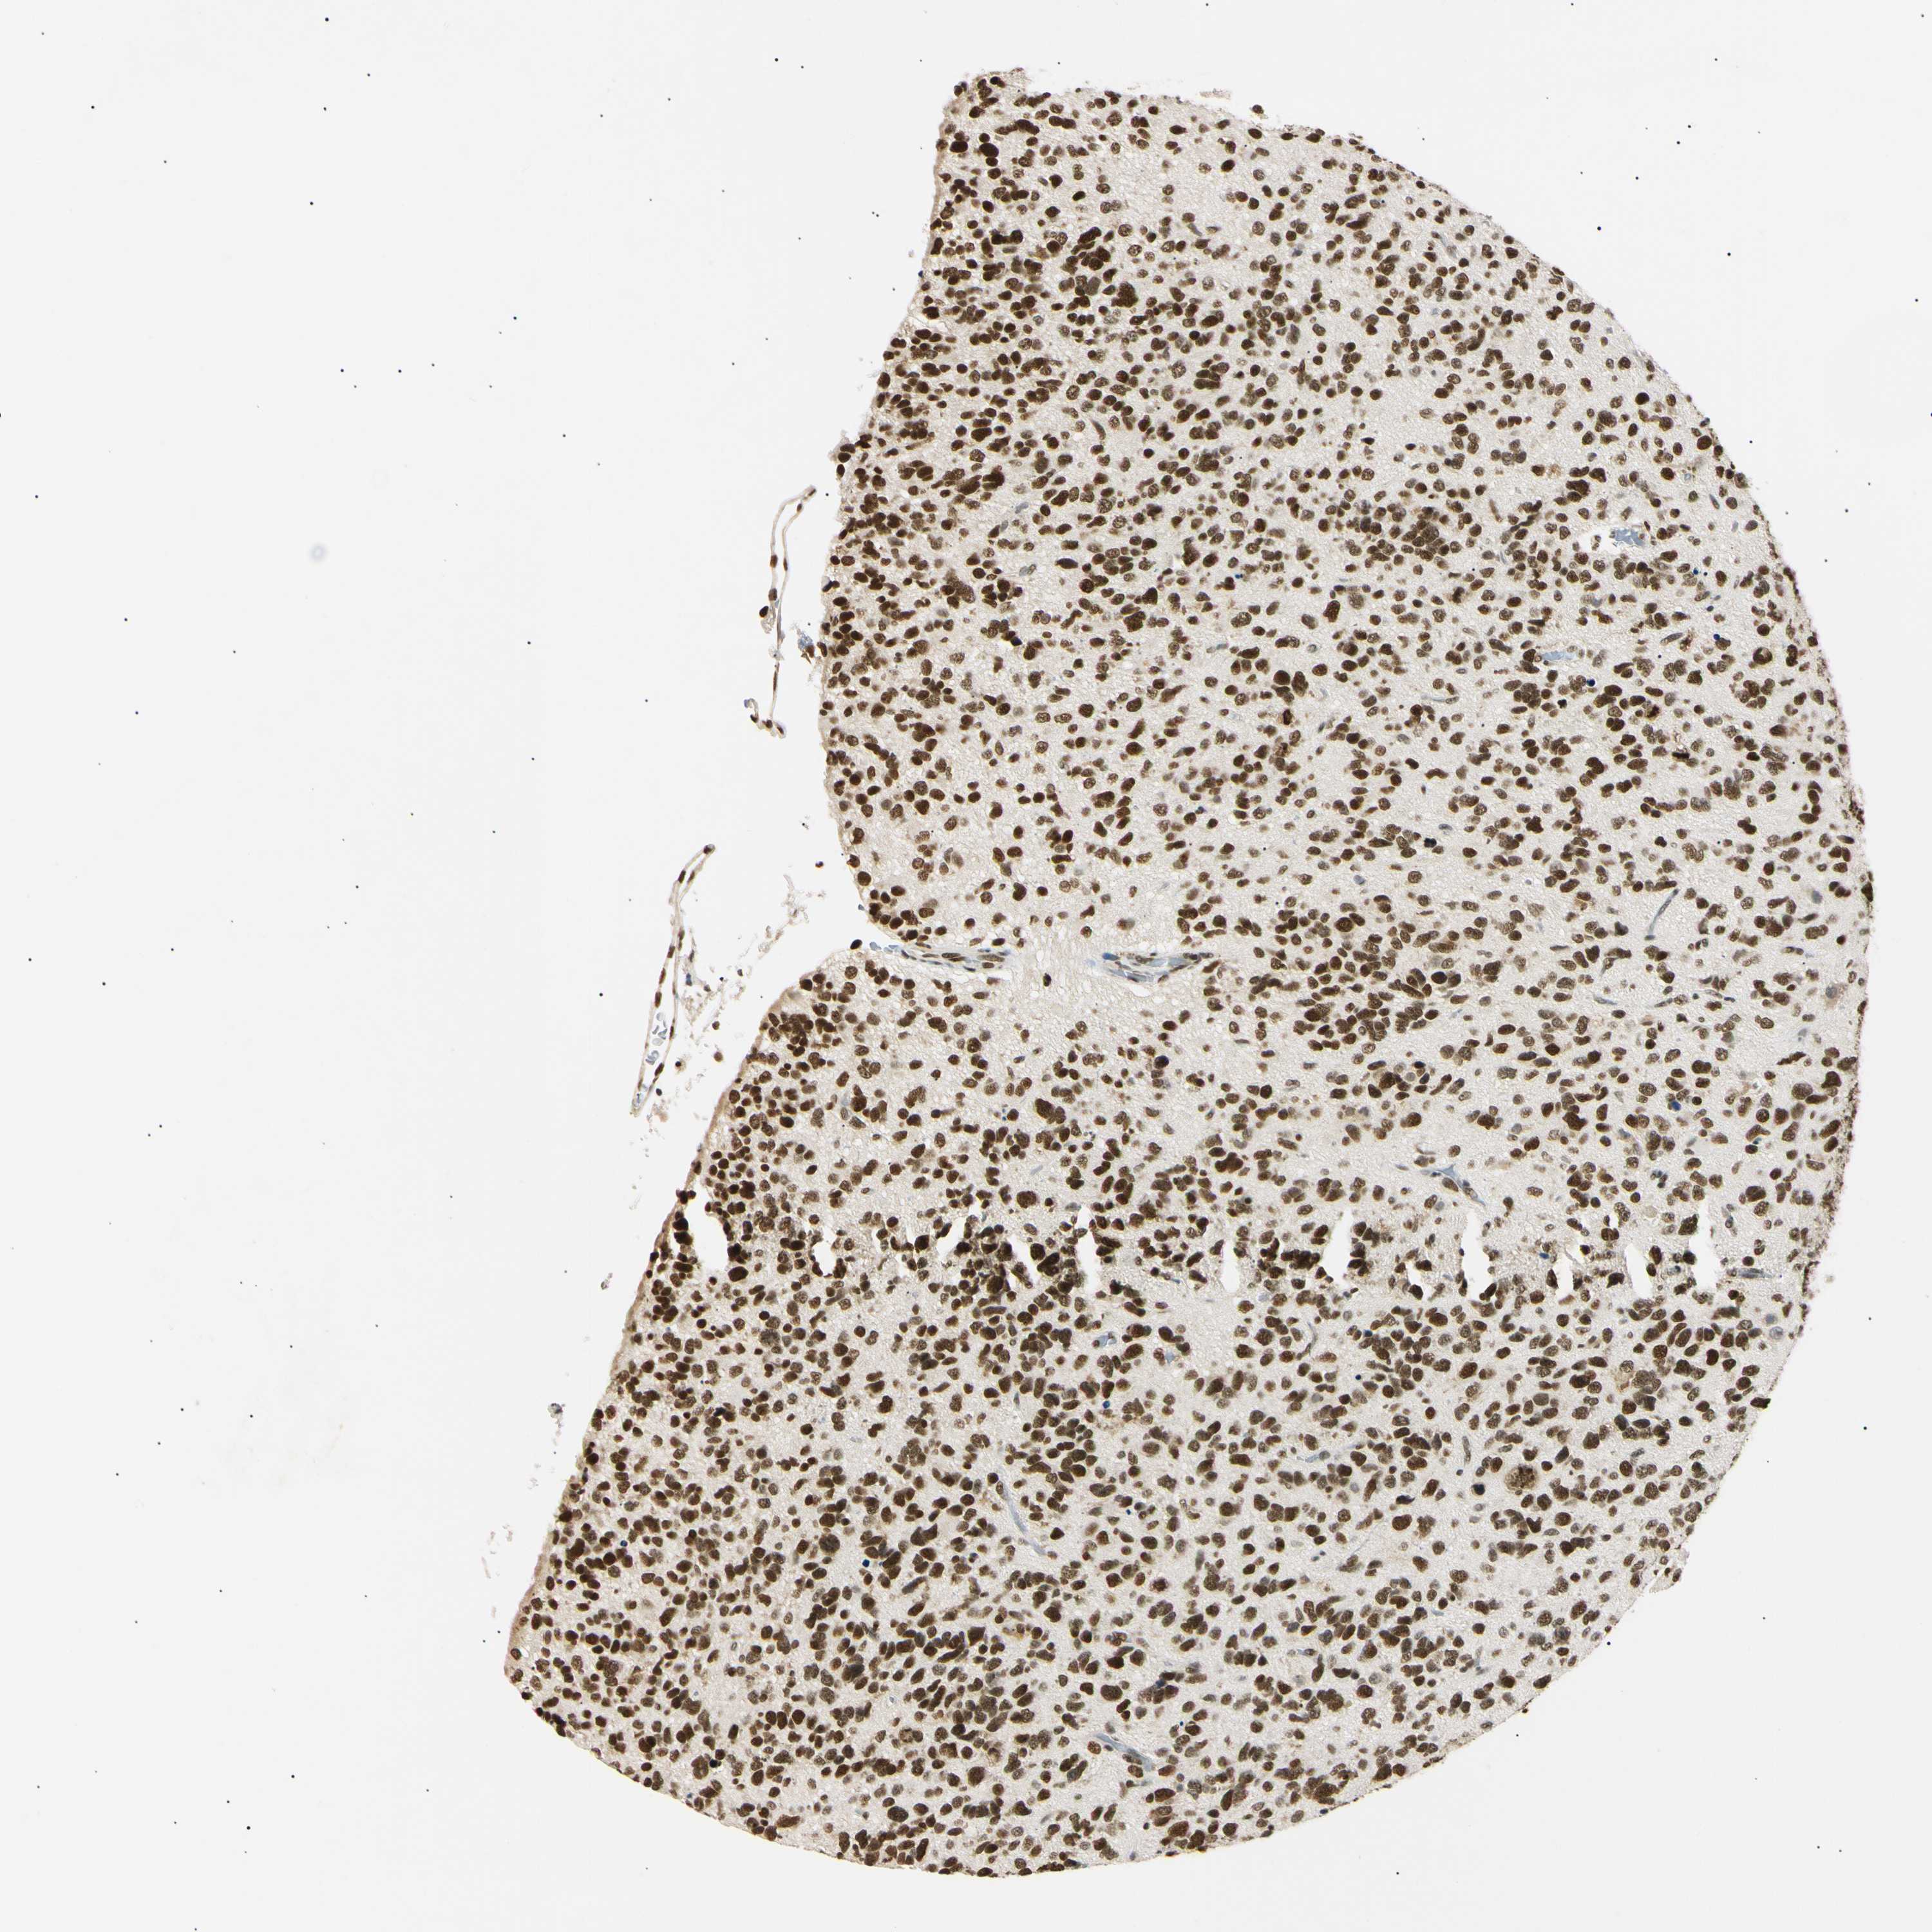

GLIOMA - Protein expressioni

A mouse-over function shows sample information and annotation data. Click on an image to view it in a full screen mode. Samples can be filtered based on level of antibody staining by selecting one or several of the following categories: high, medium, low and not detected. The assay and annotation is described here.

Note that samples used for immunohistochemistry by the Human Protein Atlas do not correspond to samples in the TCGA dataset.

Antibody stainingi

Antibody staining in the annotated cell types in the current human tissue is reported as not detected, low, medium, or high, based on conventional immunohistochemistry profiling in selected tissues. This score is based on the combination of the staining intensity and fraction of stained cells.

Each image is clickable and will lead to virtual microscopy that enables deeper exploration of all samples and also displays staining intensity scores, fraction scores and subcellular localization as well as patient and tissue information for each sample.

Antibody HPA008751

Antibody CAB005227

Staining

High

Medium

Low

Not detected

Intensity

Strong

Moderate

Weak

Negative

Quantity

>75%

75%-25%

<25%

None

Location

Nuclear

Cytoplasmic/membranous

Cytoplasmic/membranous,nuclear

Glioma, malignant, High grade

Glioma, malignant, Low grade

Glioma, malignant, NOS